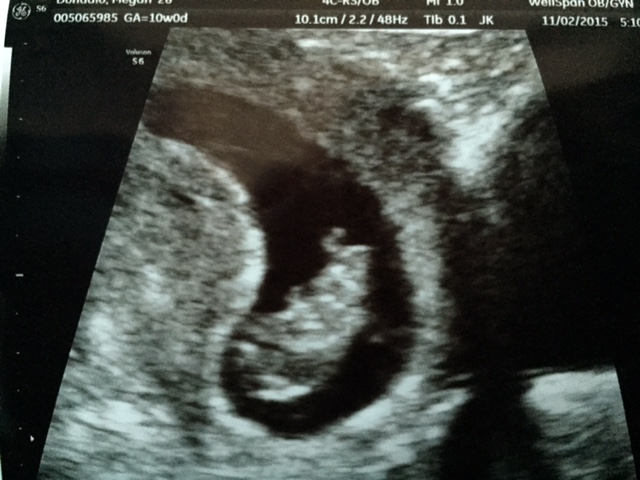

Had my first ultrasound today- our little person waved! And we were also in for a surprise- measuring about 10 weeks instead of the 8 I thought I was. Can't believe I'm already 25% done with this pregnancy!

Whew, what a relief to see that baby and that flickering heartbeat! Measured 10w1d (originally thought I was 9w3d) and have a new dd of June 2nd. Hooray! Congrats to all the mamas "meeting" their babies for the first time! Nothing like it, is there?